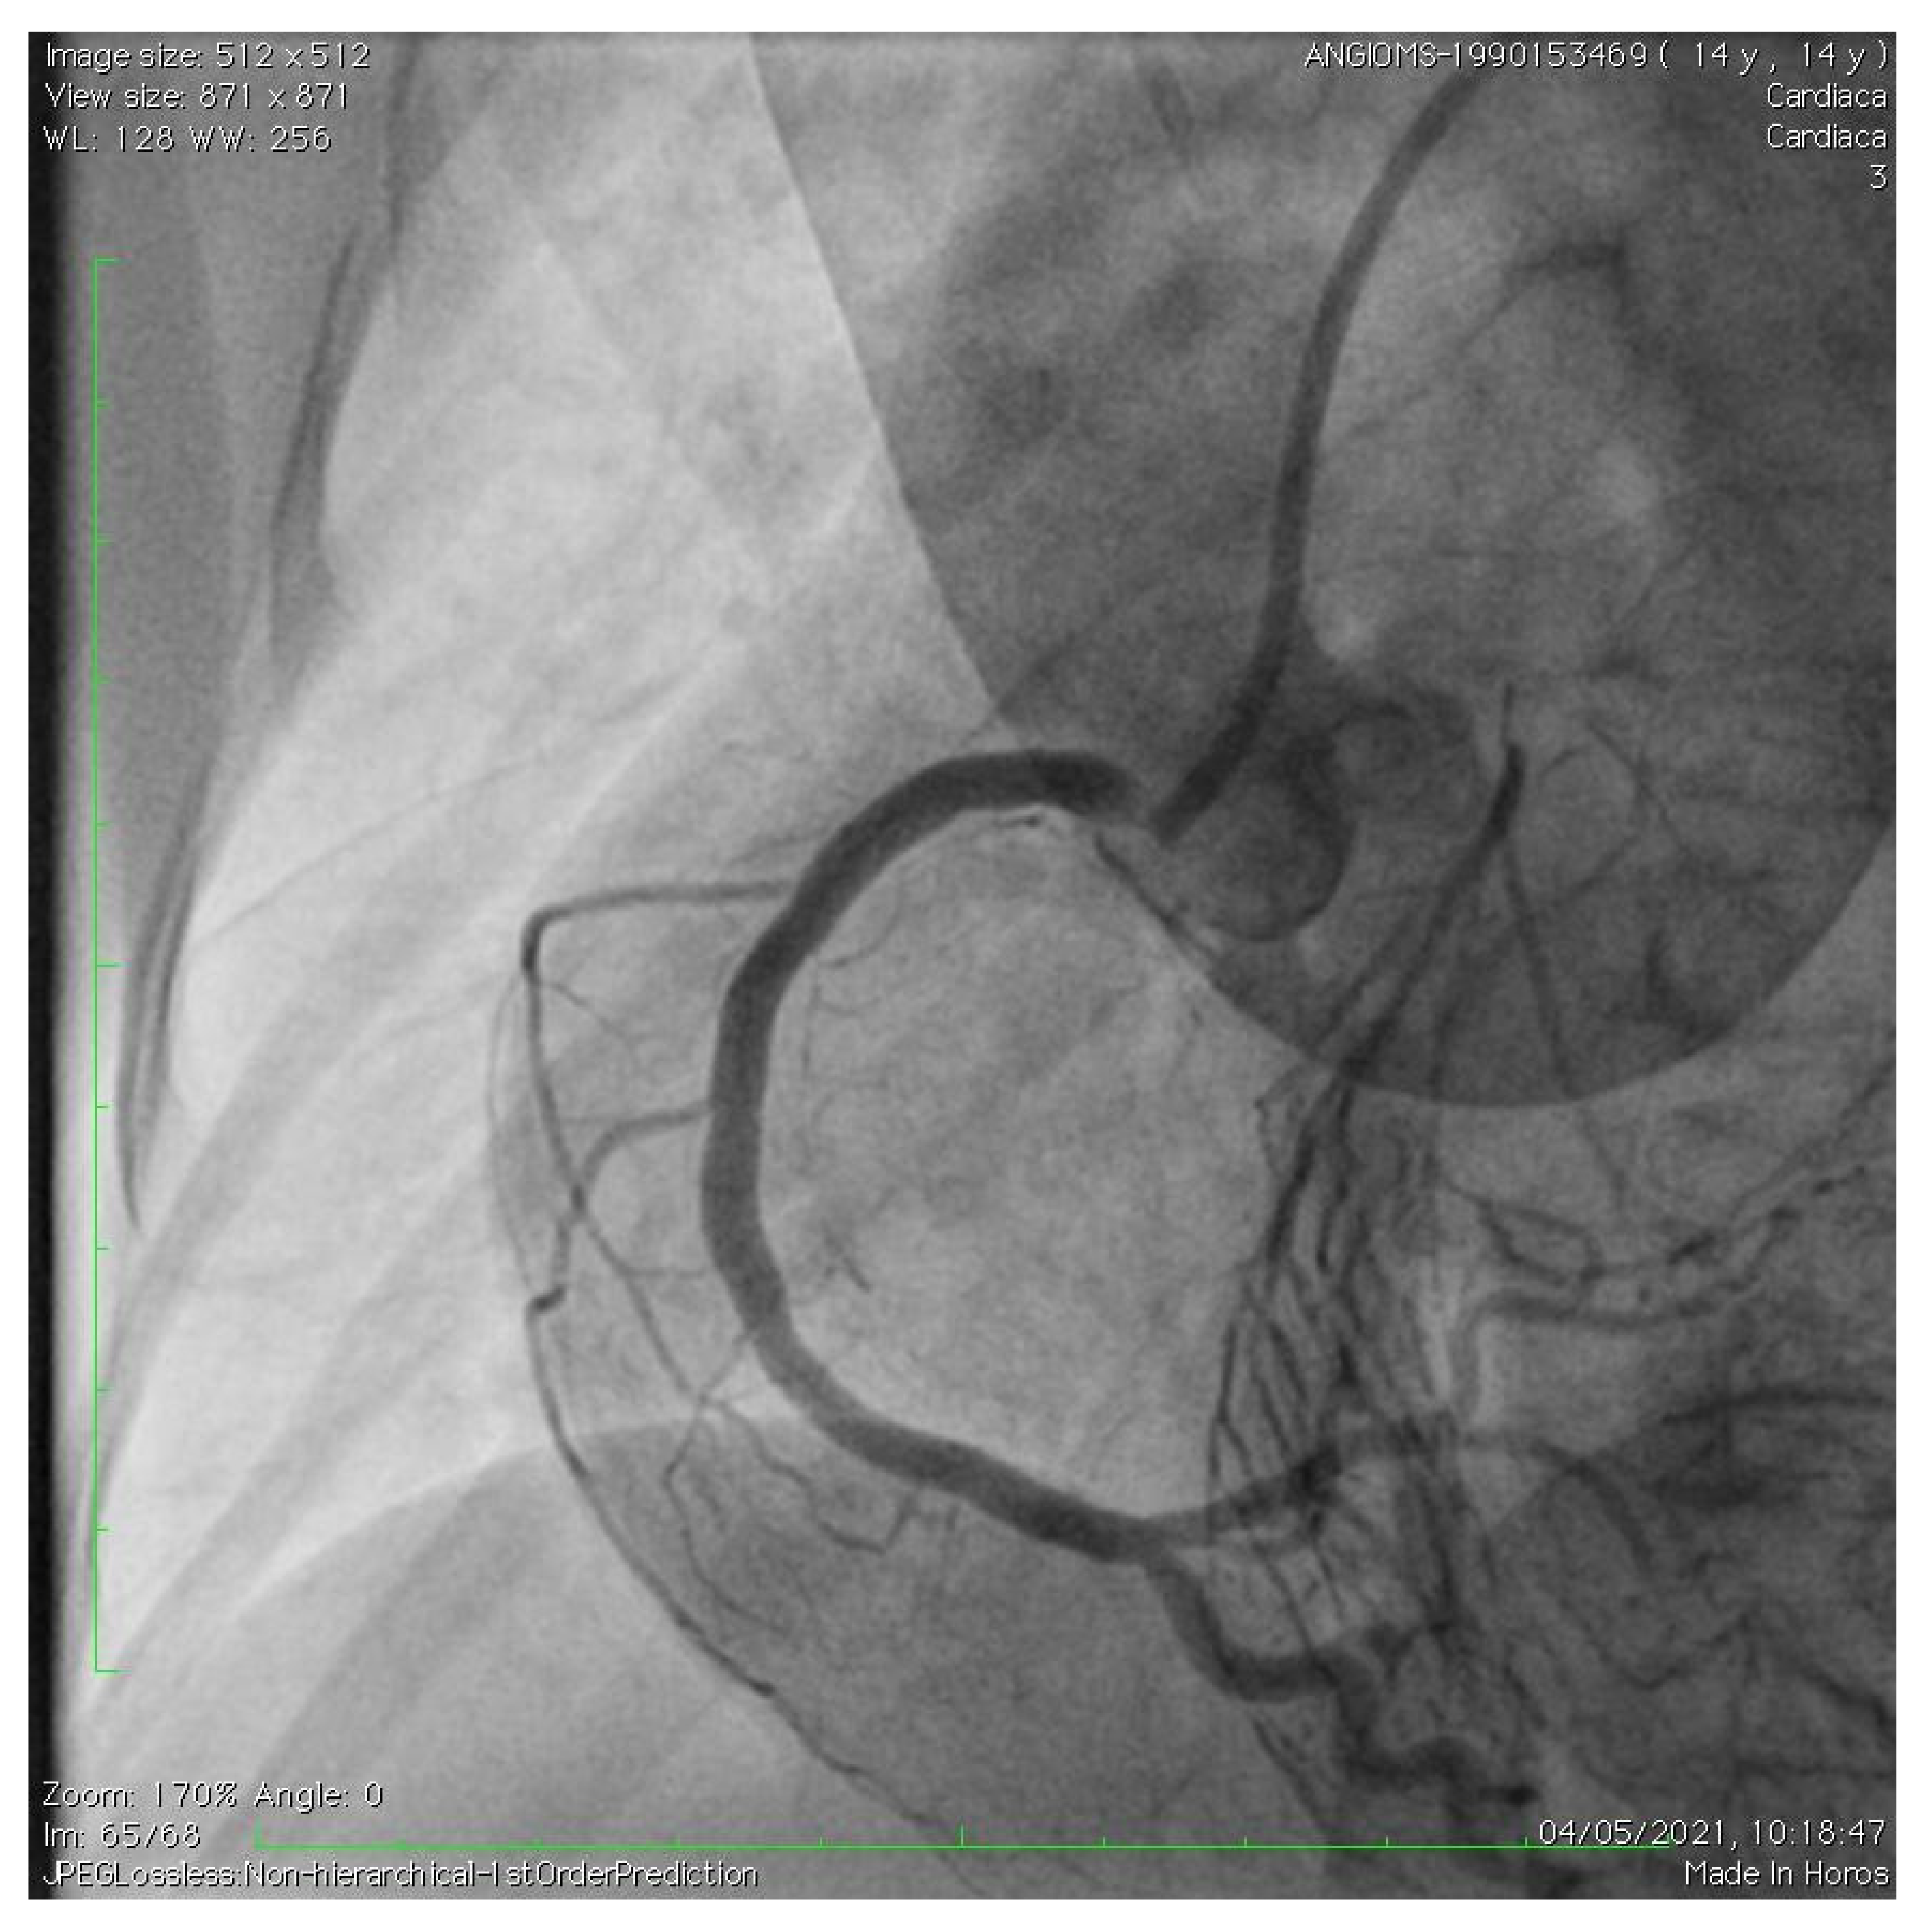

Acute Coronary Syndrome Treated with Percutaneous Coronary Intervention in Hutchinson–Gilford Progeria

2. Case Description

De Simone, L.; Chiellino, S.; Spaziani, G.; Porcedda, G.; Calabri, G.B.; Berti, S.; Favilli, S.; Stefani, L.; Santoro, G. Acute Coronary Syndrome Treated with Percutaneous Coronary Intervention in Hutchinson–Gilford Progeria. Children 2023, 10, 526. https://doi.org/10.3390/children10030526